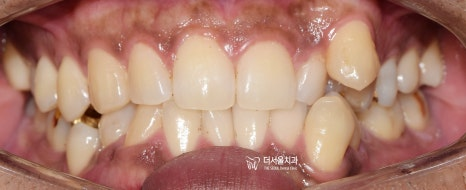

치아 삐뚤거림, 총생, Crowding 이 있는경우 어떻게 개선하나요?

총생은 턱의 크기에 비해서 치아 크기가 크고 치열이 맞지 않아서 서로 겹쳐 있는 상태를 말합니다. 흔히 말하는 덧니도, 총생의 […]

안녕하십니까, 박현준 원장입니다. 오늘은 송곳니 덧니 에 대해서 설명해 드릴까 합니다. 송곳니 는 유치에서 영구치로 교환하는 시기에 덧니